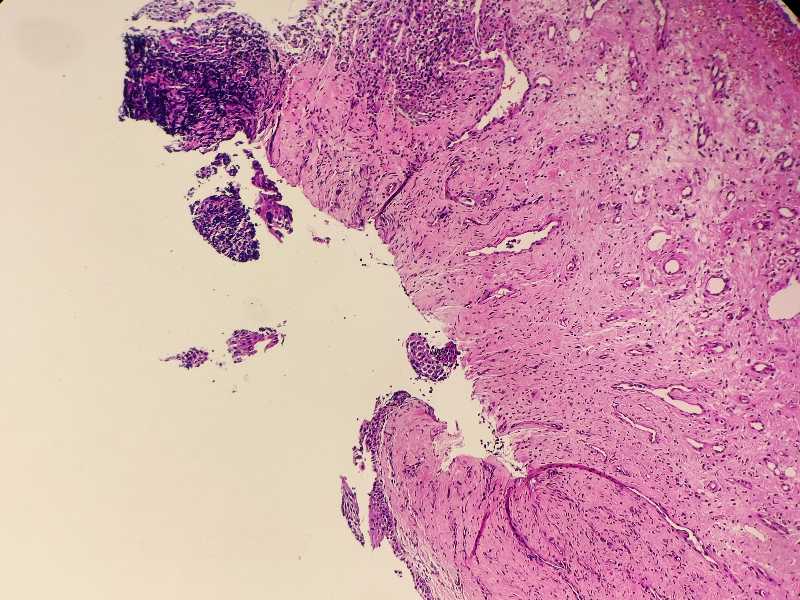

女59岁宫颈活检HPV58+